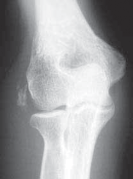

Chapter 31 Knee Arthroscopy: The Basics Steven A. Aviles and Christina R. Allen DEFINITION Knee arthroscopy…